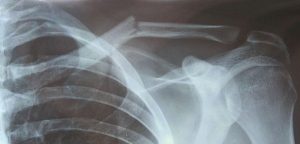

Al fine di individuare la posizione e la gravità della frattura, il medico vi farà eseguire una radiografia. Spesso verranno eseguiti i raggi X di tutta la spalla per verificare la presenza di ulteriori lesioni. Se altre ossa sono rotte, il medico può ordinare una TAC per vedere le fratture più nel dettaglio.